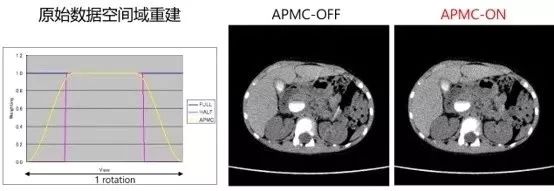

APMC呼吸伪影校正,应对屏气不好的患者